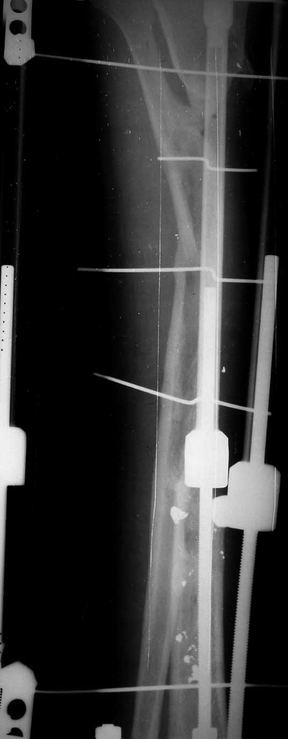

Re: Дефект большеберцовой кости - что делать? Ваше

У нас не задумываясь провели бы vascularized fibular graft.

Можно было split fibula transfer, но для этого

необходима интактная малоберцовая.

Предложенный Александром вариант, кейдж плюс стержень - неплохая идея, уменьшает срок восстановления, и без наружных атрибутов фиксатора.

Хотя для уменьшения размера дефекта (кейдж) можно было предложить предварительную однофокальное удлинение в проксимальном метафизе, потом применение стержня.

Стержень можно забить через голеностоп в таран, тогда удлинится и усилится короткий дистальный конец.

Если смелость больной достаточна для аппаратного лечения, тогда другой вариант, комбинация удлинения в проксимальном отделе большеберцовой и утолщения малоберцовой в нижней трети, где диаметр малоберцовой позволяет.

Для сокращения времени малоберцовую можно расширить быстрыми темпами, а в образовавшуюся щель ввести костный графт.